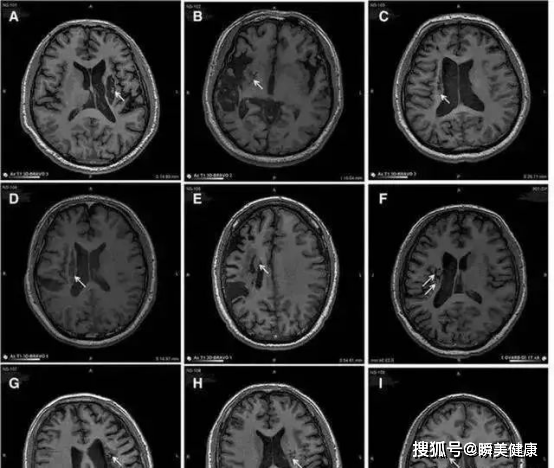

2019年我国解放军总医院发表于《干细胞转化医学》研究显示,神经干细胞回输有助于脑卒中偏瘫患者运动功能恢复。

9名偏瘫患者接受人源神经干细胞脑内回输后,影像学显示植入区出现新的神经组织,证明其有一定临床益处。

△9例患者的影像学显示病变区域的组织发生明显变化